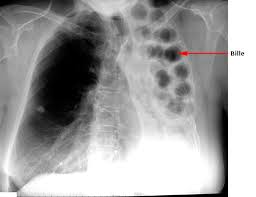

Le Sénégal à l’instar de la Communauté Internationale célèbre la journée mondiale de lutte contre la Tuberculose ce Mardi 24 mars 2014 à Kaffrine. Le thème retenu est: « Atteindre les manquants ». L’objectif est de contribuer à l’atteinte l’objectif global des trois millions au niveau mondial. Neuf (9) millions de personnes par an tombent malades de la tuberculose. Un tiers d'entre eux ne reçoivent pas les services antituberculeux qu'ils méritent. Selon le communiqué du Ministère de la Santé et de l’Action Sociale (MSAS), la Tuberculose demeure aujourd’hui une épidémie dans une grande partie du monde, entrainant plusieurs millions de décès, la plupart du temps dans les pays en développement.

Pour la tutelle, « la Journée Mondiale de lutte contre la Tuberculose, nous appelle à un effort mondial visant à trouver, traiter et guérir les personnes non accessibles aux soins ». La cérémonie officielle prévue ce 24 mars à Kaffrine, est placée sous la Présidence de Madame le Ministre, le Professeur Awa Marie Coll Seck.